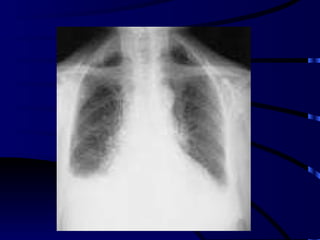

Diagnostico Rx St de tórax – Rx tórax decúbito lateral Ecografía pleural TAC de torax

Diagnostico Rx Stde tórax – Rx tórax decúbito lateral Ecografía pleural TAC de torax